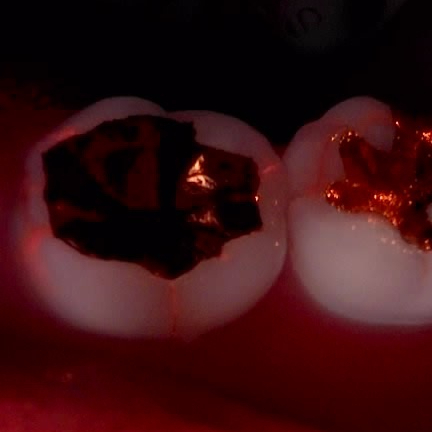

Q-ray라고 하는 <정량광형광기> 진단장비를 활용하면

세균이 드나든 흔적을 이렇게

붉은 색으로 나타내 보여줍니다.

치아 사이로 세균이 어떻게 드나들까요?

그건 세균이 드나들 수 있을만큼

세균 입장에선 굉장히 큰 틈이 벌어져 있다는 뜻이고

결국 치아에 금(crack)이 갔다는 이야기죠.

큐레이 카메라로 치아를 찍어보았더니

오래 전에 금(gold)으로 때운 치아 주변으로

자글자글 온통 다 크랙이 가 있어서

자극이 신경까지 전달된 것으로 판단했습니다.